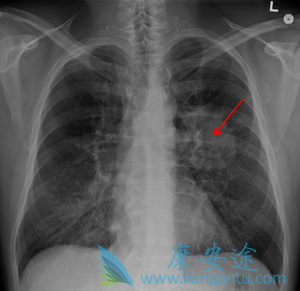

肺癌骨转移